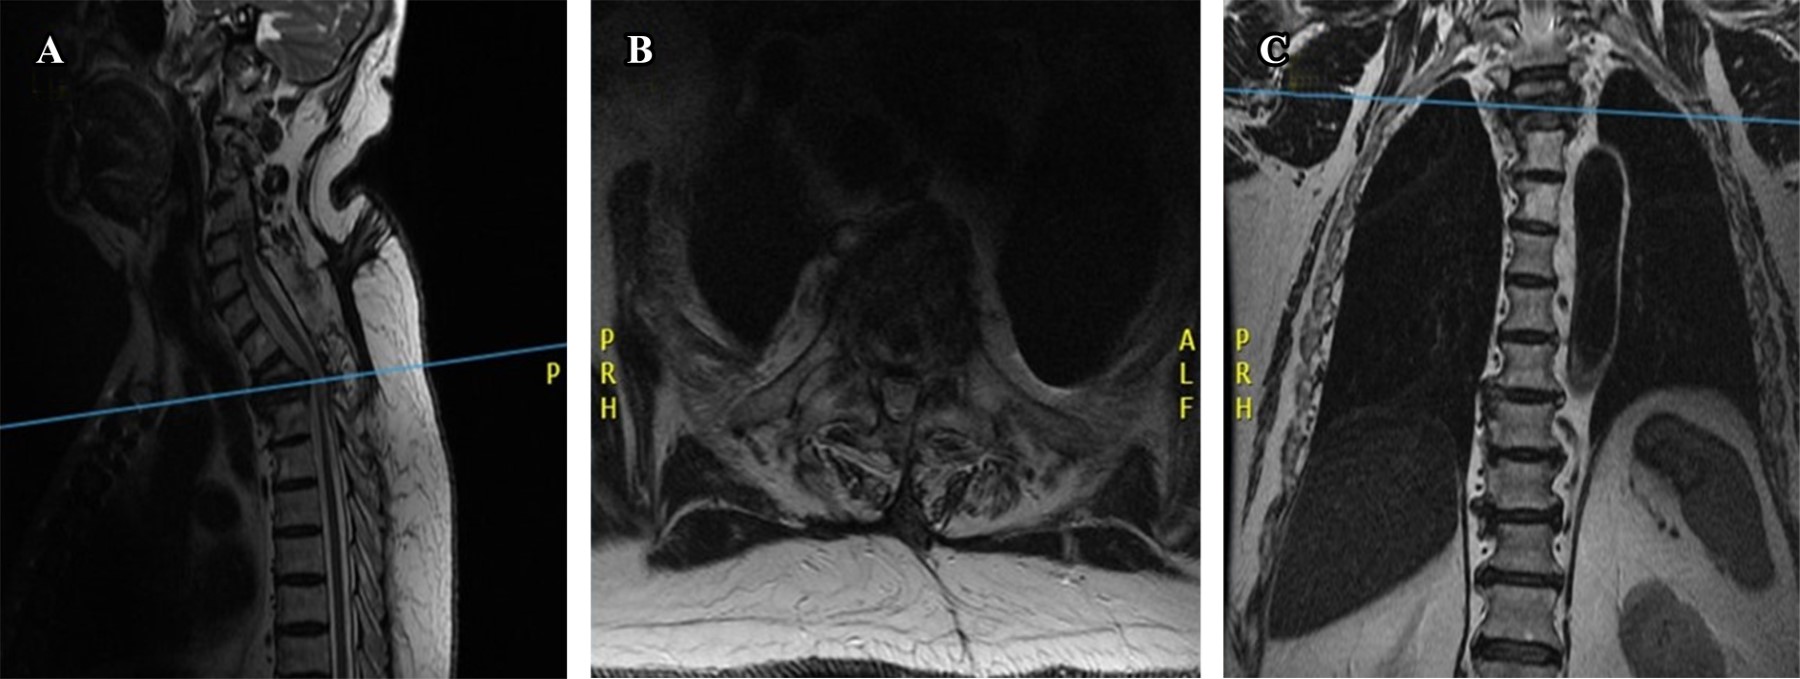

Paciente con espondilodiscitis que presentó deformidad cifótica con compromiso neurológico a nivel torácico superior, quien fue tratado con un nuevo abordaje torácico anterior infraclavicular derecho, como nueva técnica quirúrgica alternativa. Varón de 72 años con deformidad en cifosis secundaria a espondilodiscitis T2-T3 ASIA "C", tratado con instrumentación cervicotorácica posterior C5 a T6 y abordaje anterior transtorácico infraclavicular derecho con colocación de cilindro expandible. Dentro de la revisión bibliográfica realizada en los buscadores no se encontraron técnicas similares a la descrita en este artículo. Dada la complejidad del abordaje quirúrgico, esta nueva técnica se describe como una nueva forma de acceder a la columna torácica superior, demostrando que el abordaje torácico anterior infraclavicular derecho es una nueva alternativa para acceder a la columna torácica superior desde T1 a T4.

Figura 4